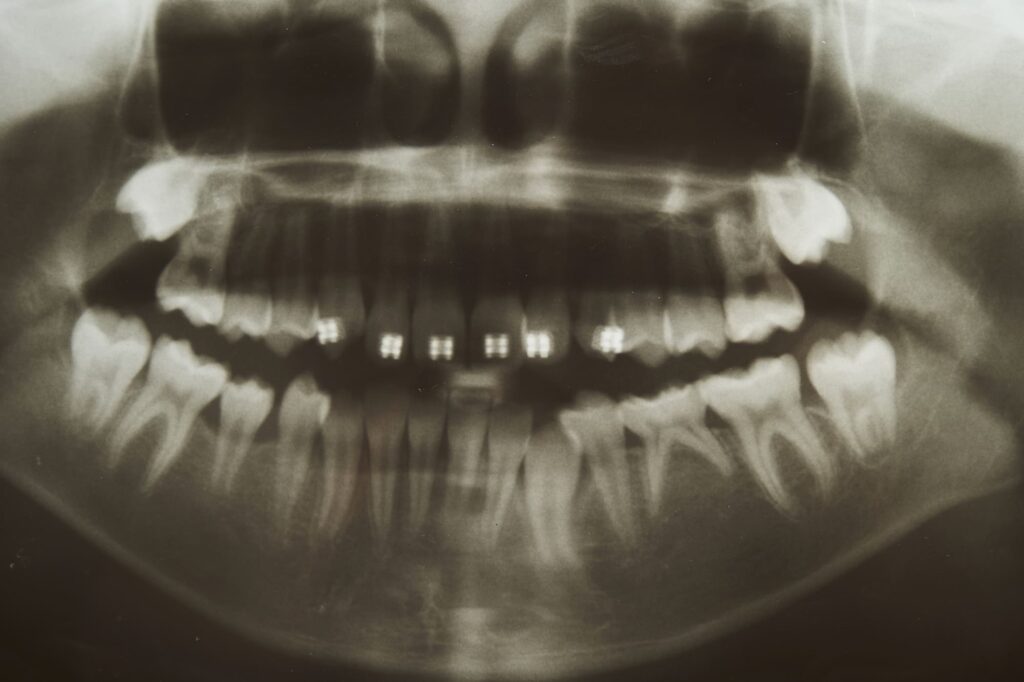

CTによる三次元的な診断

二次元レントゲンでは確認できない小さな病変も、CTを用いることで三次元的に把握できます。問題部位の見落としを防ぐことで、より確実な診断と治療計画の立案につながります。

CT画像

レントゲン画像